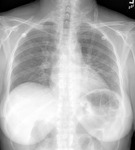

Posteroanterior chest x-ray showing severe, bilateral pulmonary interstitial infiltrates with pneumatoceles

From the collection of Matthew Gingo, UPMC